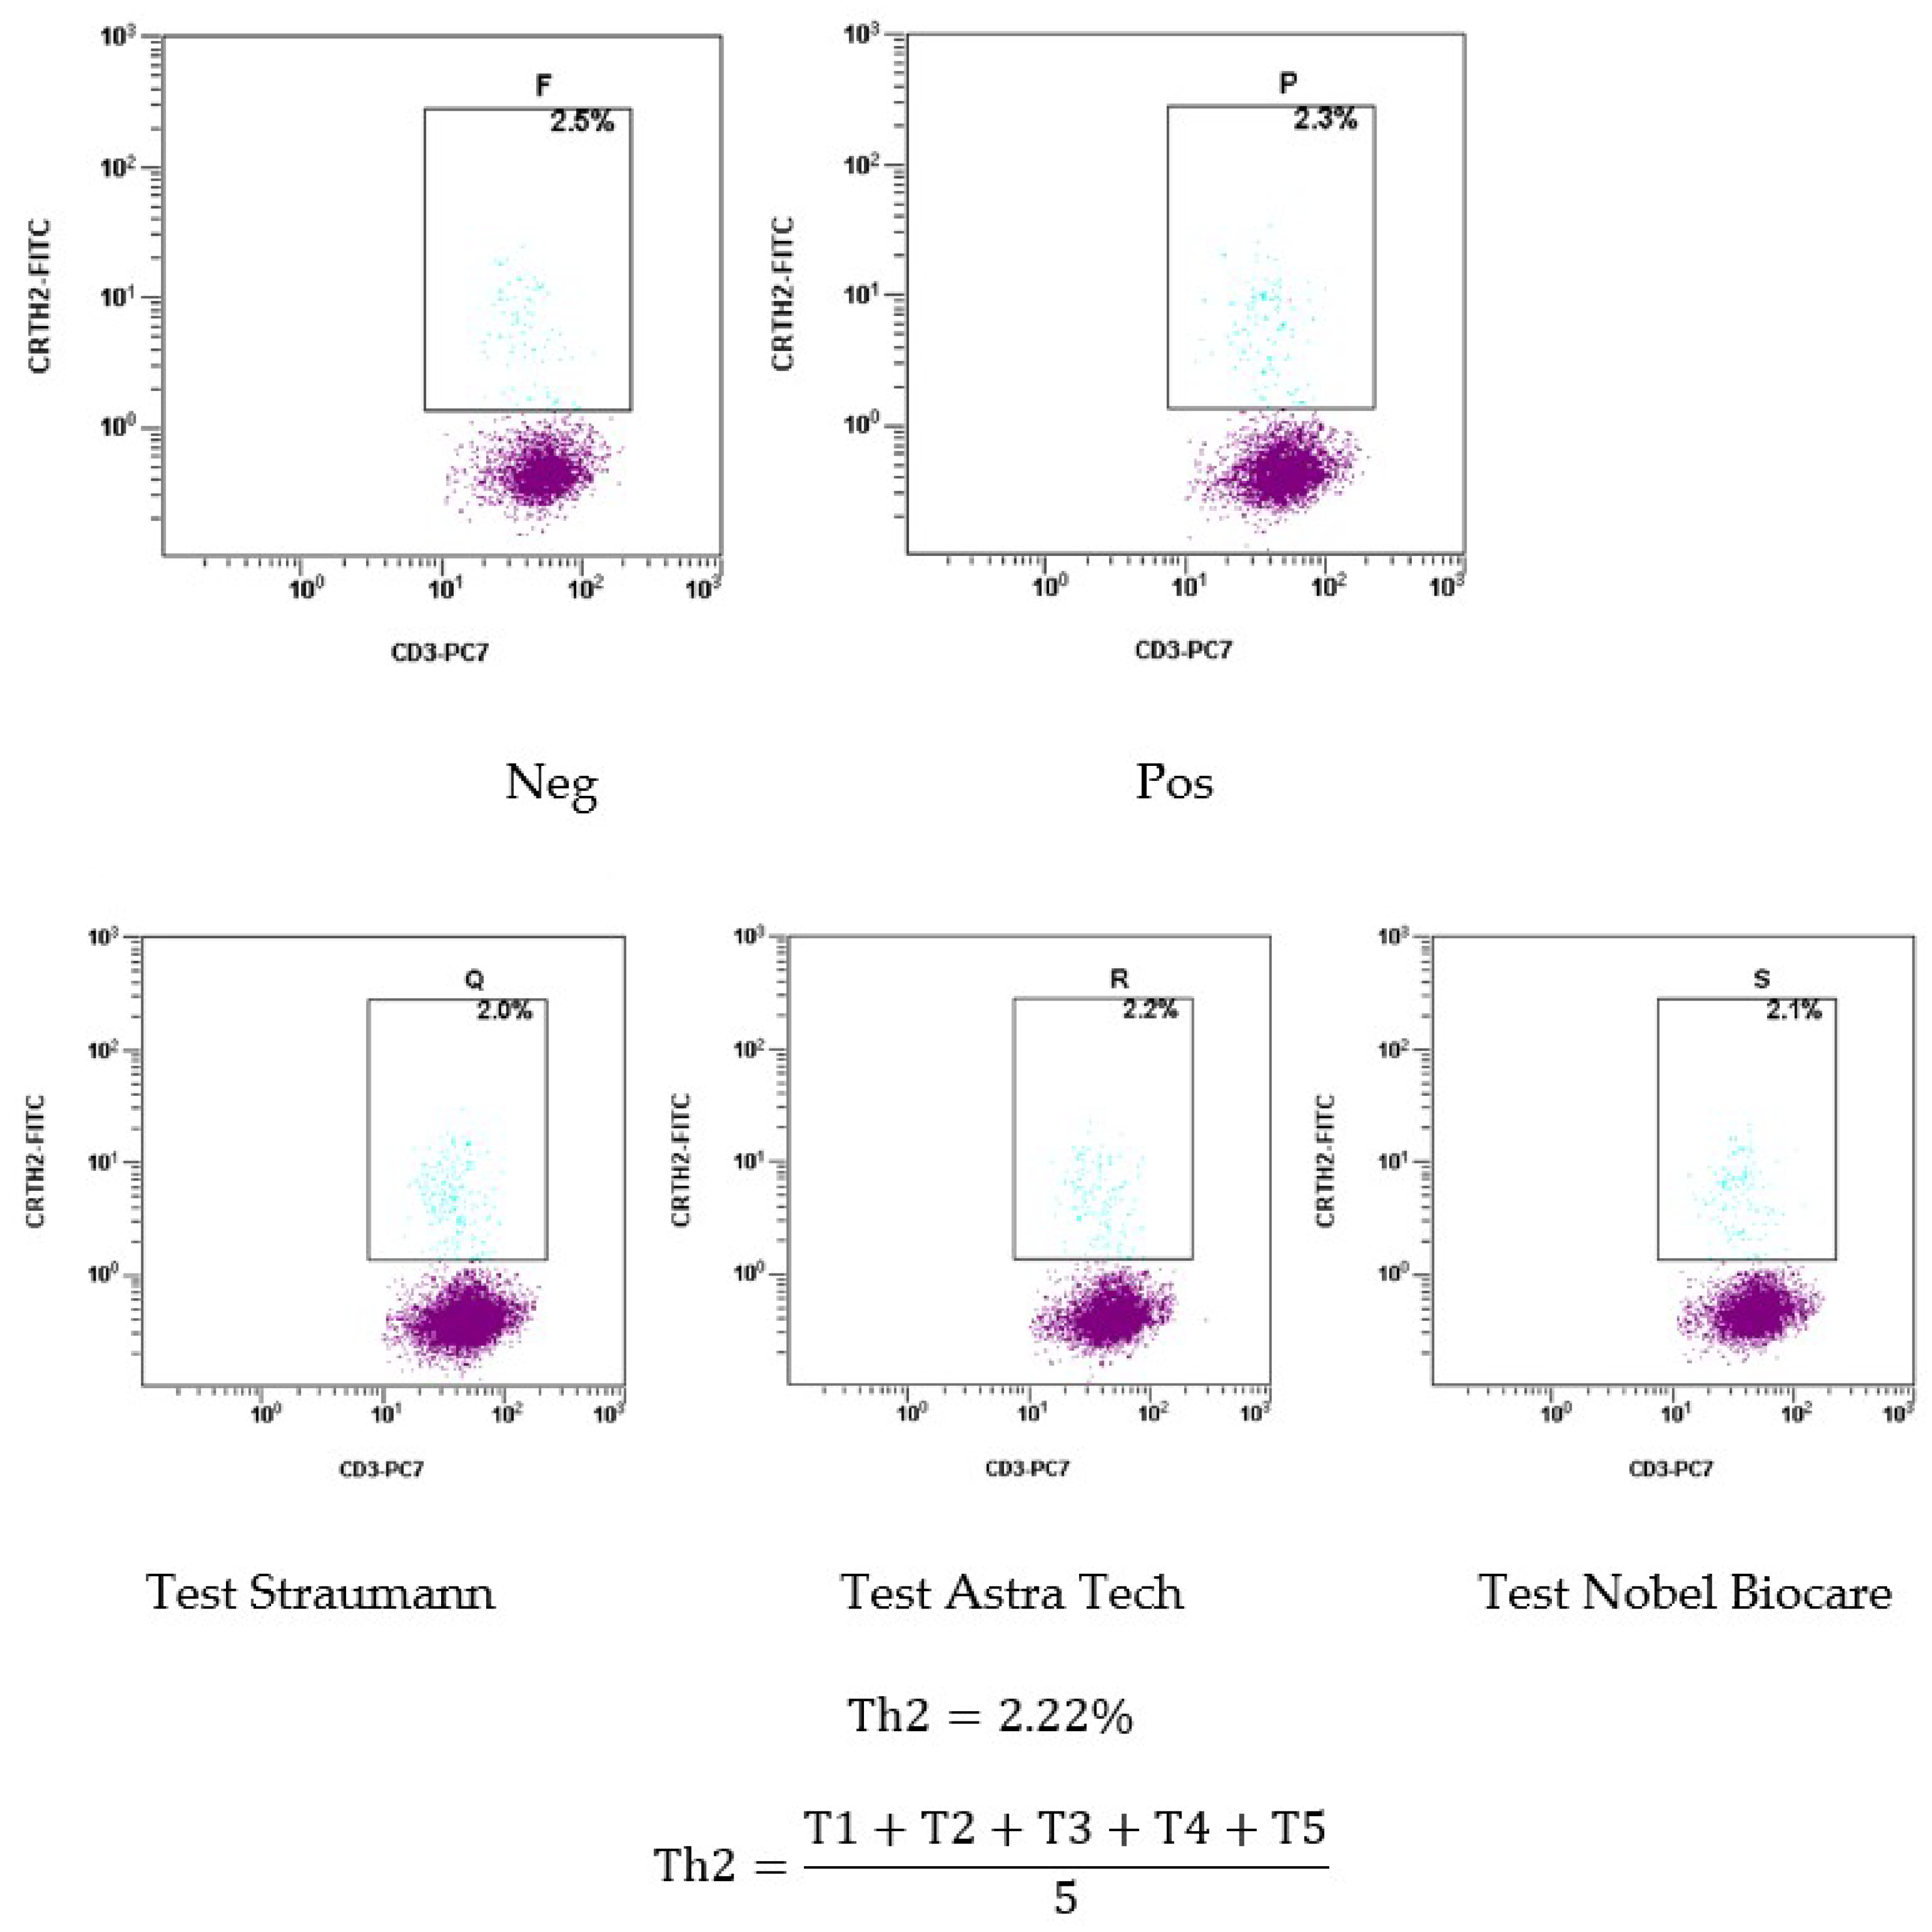

2.1.3. Results of the Basophil Test of Patient Sh. (Female, 52 Years Old)

4.6. Methodology for the Basophil Test